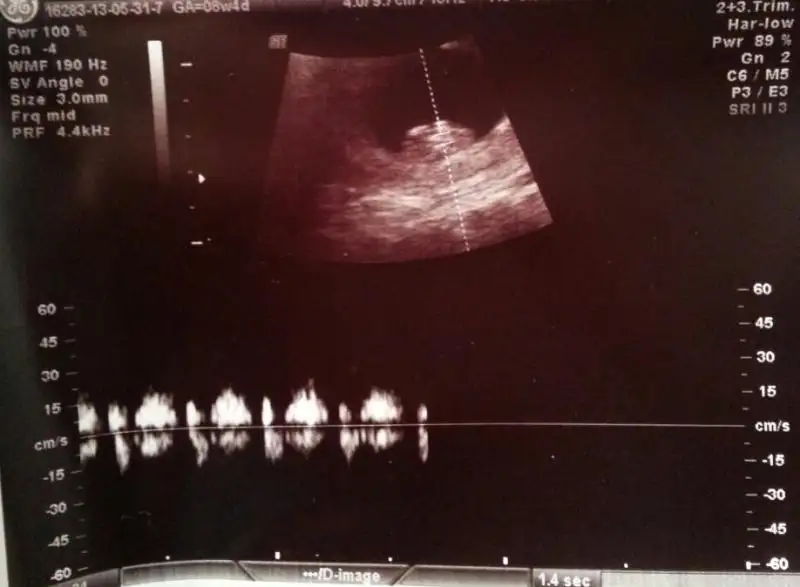

Kızlarr biz kontrolümüzden geldik. Çok şükür herşey yolunda. Ellerimiz kollarımız belli olmaya başlamış. Geçen sefer arada 4 günlük bir fark vardı dah büyük çıkmıştı bebişim. Bu defa sat la aynı çıktı. 8+4 Olmuşuz. 1 Ay sonra tekrar gidicez. Şuana kadar hiç kilo almadığım hatta 2 kilo verdiğim için kızdı doktorum. Bir sonraki gelişine kilo al da gel dedi.Bizden haberler bunlar. Çok şükür bu bayram çifte bayram yaşayacağız.